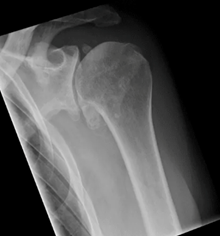

Shoulder osteoarthritis (omarthrosis) is a degenerative disease in which the joint cartilage gradually wears away. This leads to pain, restricted movement and a noticeable reduction in quality of life. Those affected often complain of pain that is typically load-dependent and an increasing restriction of movement.

Osteoarthritis of the shoulder joint (omarthrosis)